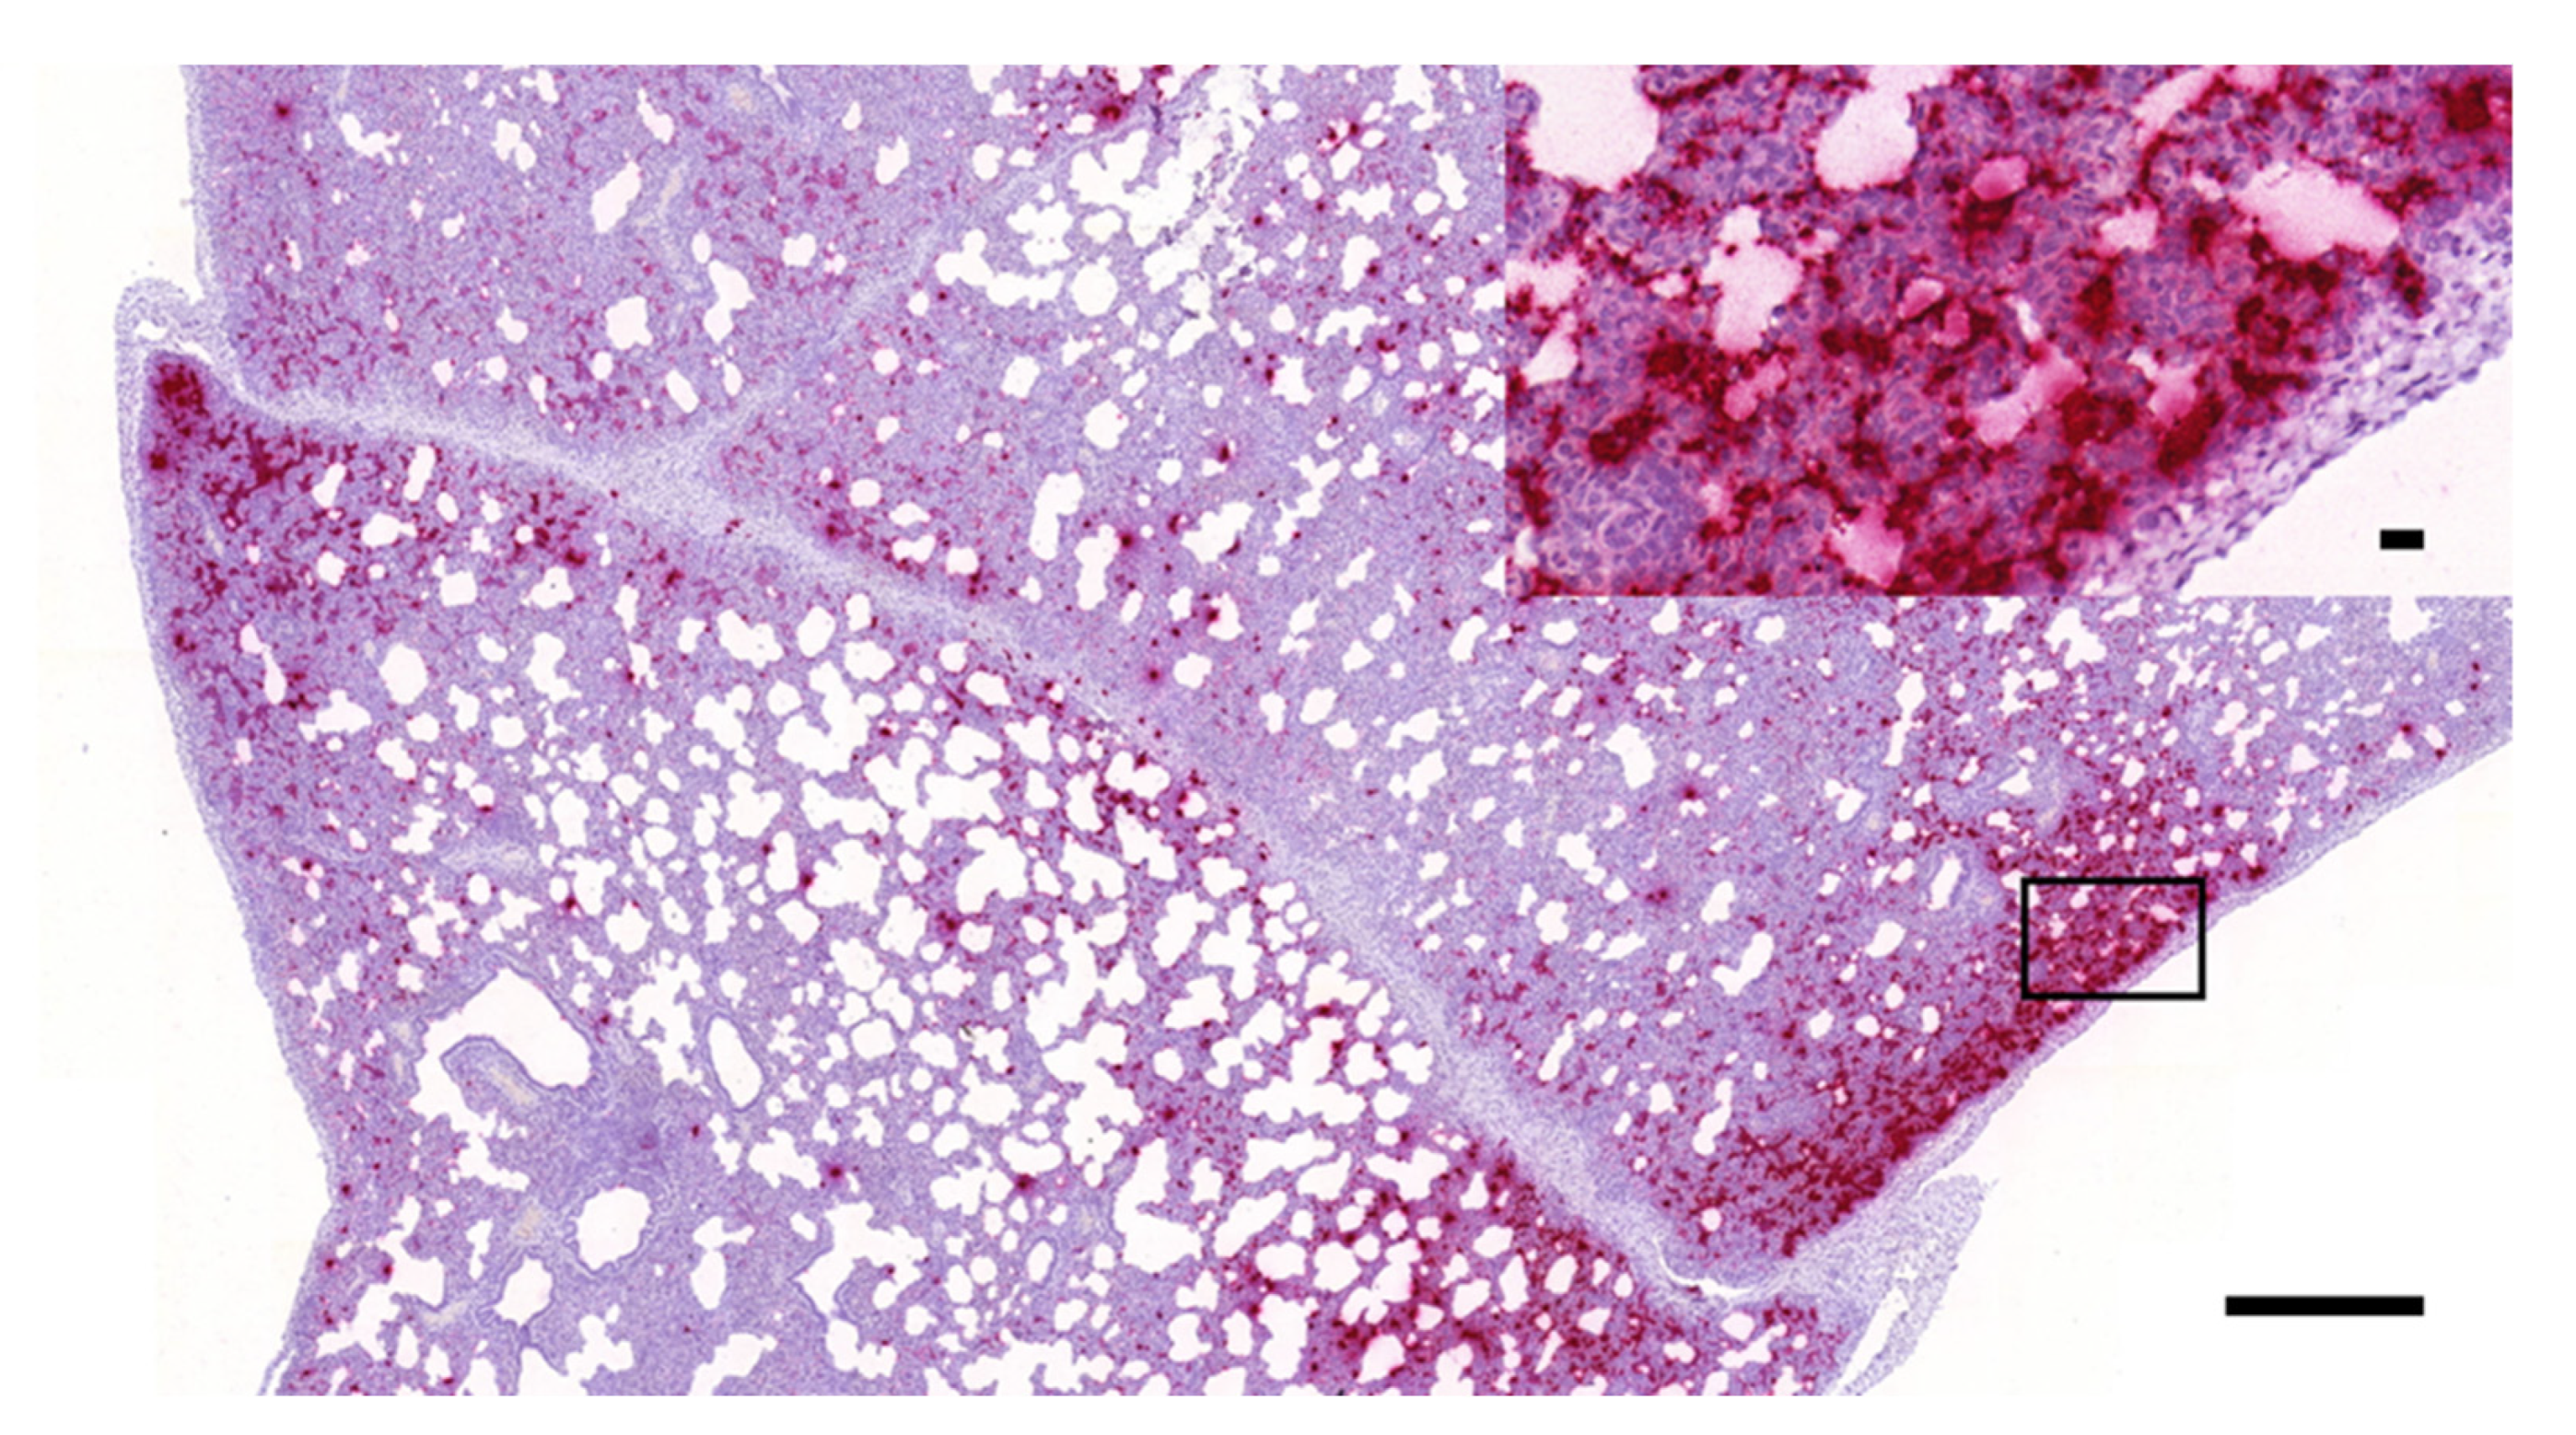

3.1. Histopathology and In Situ Hybridization

3.3. Digital Image Analysis